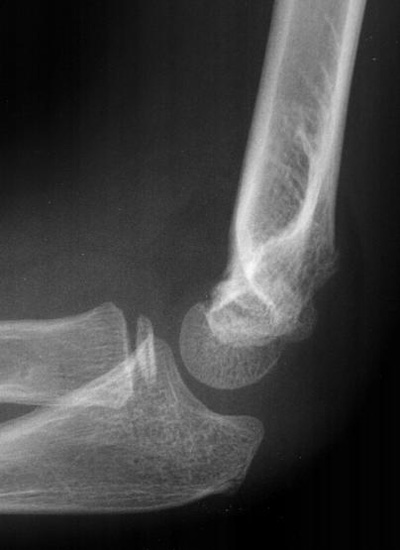

Notice that this is not an ideal lateral making interpretation of the anterior humeral line difficult; however the radius should bisect the capitellum on all views regardless of adequacy; also note the posterior fat pad.

An abnormal radio-capitellar line

On both views the radius fails to bisect the capitellum indicating an obvious radial head dislocation. Also note the anterior and posterior fat pads, as well as the obvious olecranon deformity. A radial head dislocation with an olecranon fracture is called a Monteggia injury.